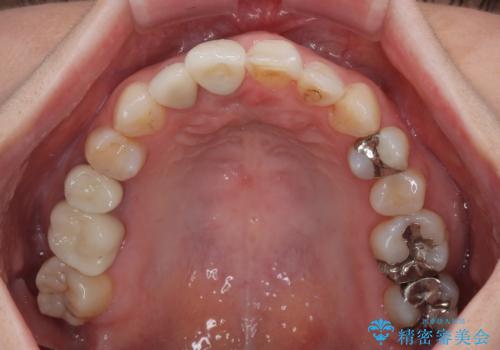

- 前歯のセラミッククランが外れてしまったとのことで来院された患者様です。

診察をしたところ、歯根に縦破折が認められ、抜歯が必要と判断されました。

抜歯、インプラント埋入、仮歯の装着が同時に可能な1DAYインプラントが適用可能と判断されたため、インプラントによる補綴治療を行うこととしました。